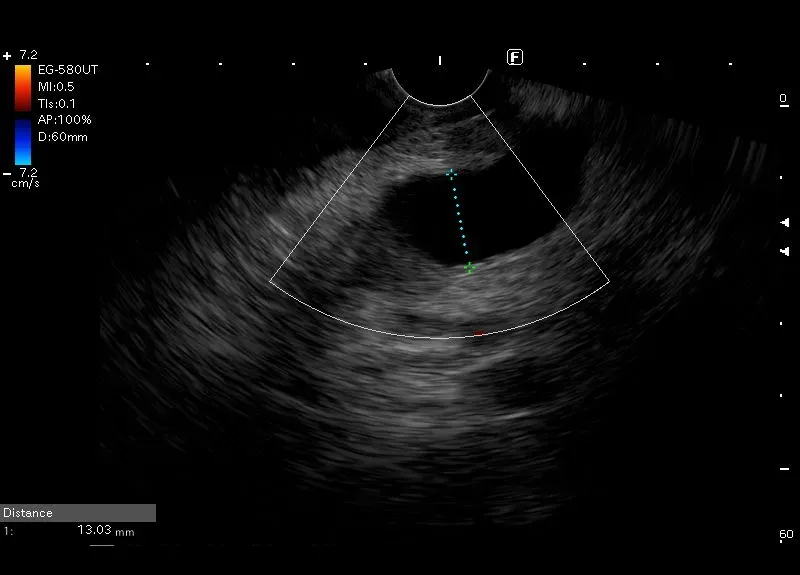

Widoczna w głowie trzustki, położona typowo, bezechowa struktura tabularna bez widocznego przepływu w opcji power doppler - poszerzony do 13 mm przewód Wirsunga, uciskany przez guz trzustki ,który na zdjęciu nie jest widoczny.